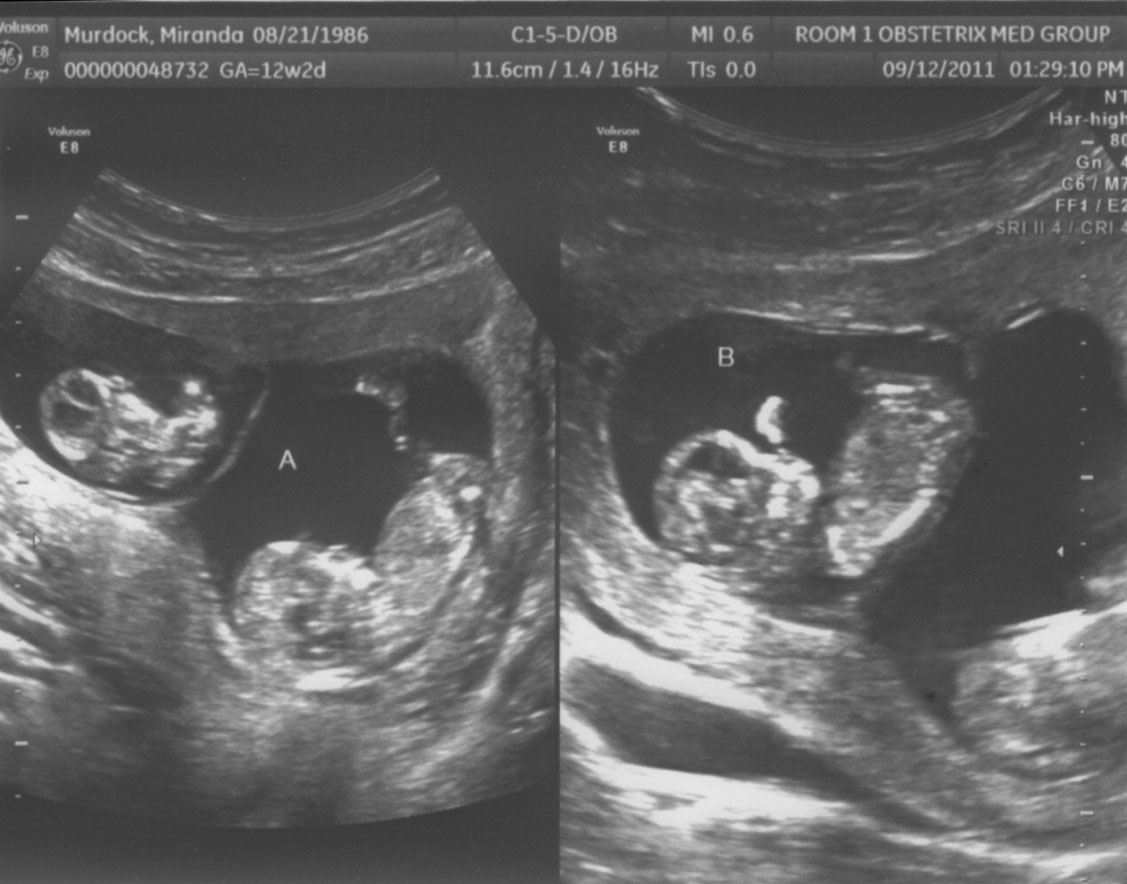

12 неделя близнецы

12 неделя близнецы 115 фото